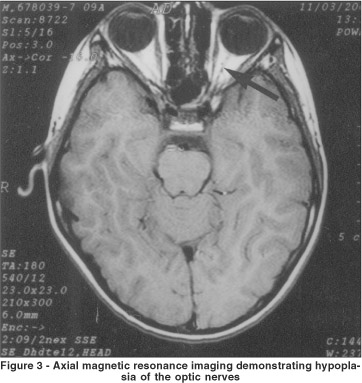

Magnetic resonance imaging revealed absence of the septum pellucidum (Figure 2), hypoplasia of the optic nerves (Figure 3) and chiasm. Endocrinologic test results (basal cortisol, adrenocorticotropic hormone, growth hormone, thyroid stimulating hormone, serum thyroxine, testosterone) were normal. A diagnosis of septo-optic dysplasia was established.

The wide spectrum of anatomical malformations of the brain and optic apparatus in SOD can be visualized by magnetic resonance imaging or computed tomography.